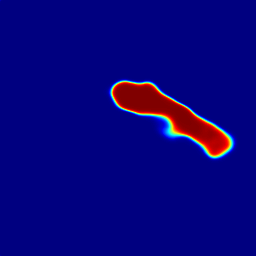

From above, the CNN sub-network processes pancreas segmentation on individual 2D image slices, delivering remarkable performance on the tested CT and MRI datasets. However, as shown in the first row of Fig. 4, the transition among the resulted CNN pancreas segmentation regions in consecutive slices may not be smooth, often implying that segmentation failure occurs. Adjacent CT/MRI slices are expected to be correlated to each other thus segmentation results from successive slices need to be constrained for shape continuity and regularization. The model for 3D object segmentation is required to be able to detect and recover abnormally lost part inside slices (see Y^τsubscript^𝑌𝜏\hat{Y}_{\tau} in Fig .4).

Refer to caption

(a) Y^τ2subscript^𝑌𝜏2\hat{Y}_{\tau-2}

(b) Y^τ1subscript^𝑌𝜏1\hat{Y}_{\tau-1}

(c) Y^τsubscript^𝑌𝜏\hat{Y}_{\tau}

(d) Y^τ+1subscript^𝑌𝜏1\hat{Y}_{\tau+1}

(e) Y^τ+2subscript^𝑌𝜏2\hat{Y}_{\tau+2}

(f) CLSTM

(g) Bi-direction CLSTM

(h) Y¯τ2subscript¯𝑌𝜏2\bar{Y}_{\tau-2}

(i) Y¯τ1subscript¯𝑌𝜏1\bar{Y}_{\tau-1}

(j) Y¯τsubscript¯𝑌𝜏\bar{Y}_{\tau}

(k) Y¯τ+1subscript¯𝑌𝜏1\bar{Y}_{\tau+1}

(l) Y¯τ+2subscript¯𝑌𝜏2\bar{Y}_{\tau+2}

Figure 4: The main construction units of the proposed RNN sub-network and its input/output segmentation sequence. The sequence of CNN sub-network outputs is shown in the first row (a-e), is taken as the input of the bi-direction CLSTM (g), which is an RNN architecture composed of 2 layers of CLSTM (f) working in opposite directions. The third row (h-l) presents the corresponding output sequence, which is sharp and clean. Note that the missing pancreatic part in Y^τsubscript^𝑌𝜏\hat{Y}_{\tau} (c), in the green dashed box, is recovered by shape continuity modeling in Y¯τsubscript¯𝑌𝜏\bar{Y}_{\tau} (j). For visual clearity, we ommit the input Y^()subscript^𝑌\hat{Y}_{(\cdot)} in the bi-direction CLSTM (g), which is same as in (f).